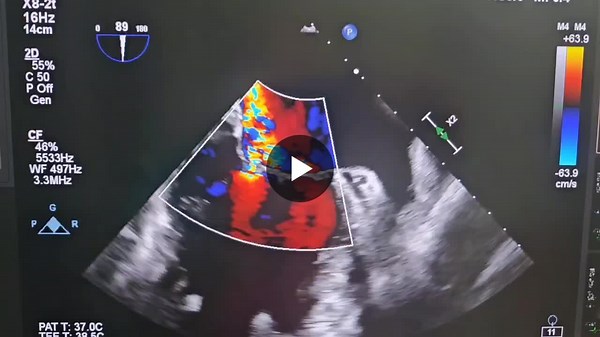

Philips Epiq - Philips Echonavigator

Cardiologie - Echolet

- Docteur Schiano

Cardiologue - Health Care